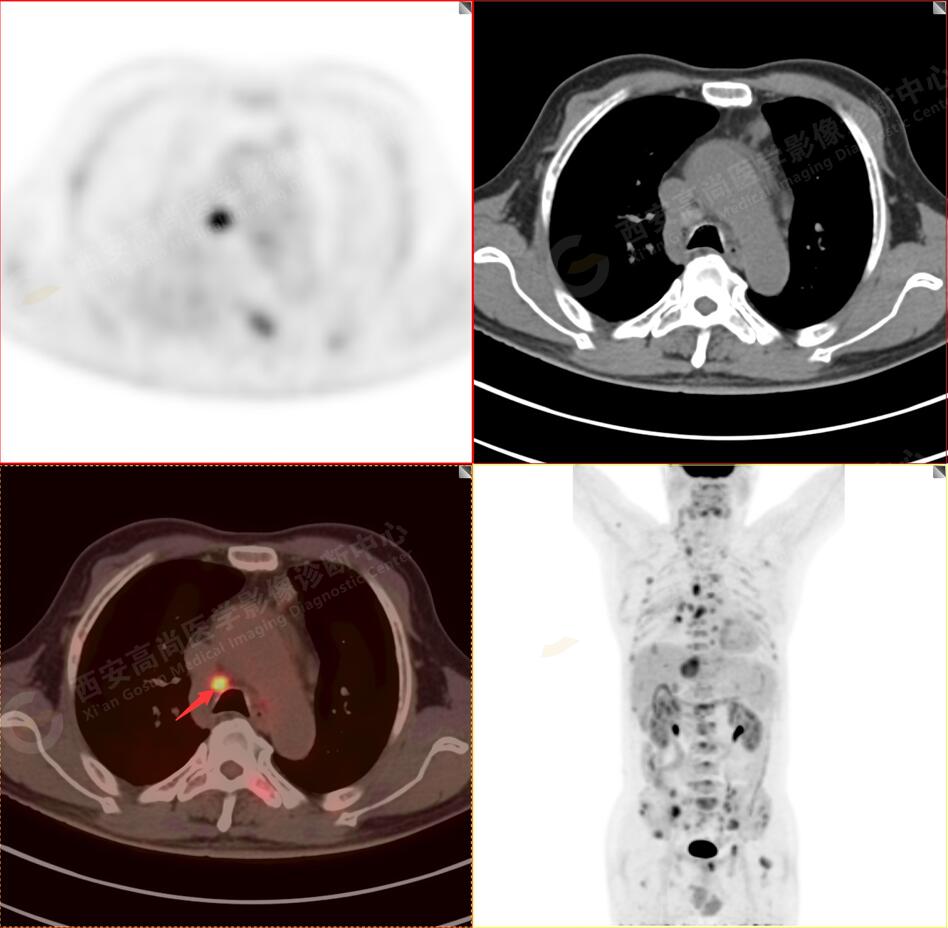

1.以下為肺內原發(fā)灶

1.右肺中葉內側段軟組織結節(jié),呈淺分葉狀,邊緣可見毛刺及胸膜牽拉征,呈FDG代謝異常增高,考慮為周圍型肺癌。